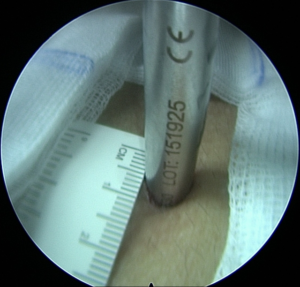

Πλάγια προσπέλαση

Πρόκειται για μια ακόμα πιο ειδική μέθοδο, κατά την οποία εισερχόμαστε μέσω του μεσοσπονδύλιου τρήματος και αποκτούμε πρόσβαση κατευθείαν στην δισκοκήλη χωρίς να χρειάζεται αφαίρεση οστικού τμήματος. Αποτελεί την λιγότερο επεμβατική μέθοδο όλων στην σπονδυλική στήλη, αφού χρησιμοποιεί φυσικά τρήματα για την είσοδο στον σπονδ. σωλήνα.